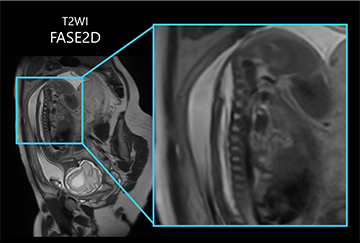

図.3 FASE2Dで撮像した胎児髄膜瘤術後の例

1.5T装置特有の検査である胎児の撮像について、特に脊髄髄膜瘤に対する胎児手術の適応判断においては、病変部の脊椎レベルを正確に同定することが求められます。そのため先生方からは、高い空間分解能や薄いスライス厚での撮像を要望されることも多くありましたが、従来は満足のいく画像を得ることが難しく、画質を求めようと再撮像を試みても、胎児が常に動いているため同じ位置での正確な撮像は非常に困難でした。

更新後は、高速撮像が可能なFASE2Dでも高画質に撮像が可能となり、良好な画質を維持したまま高い空間分解能や薄いスライス厚での撮像を短時間で実現できるようになり、再撮像の回数が減ったため、現場として非常に助かっています(図.3)。